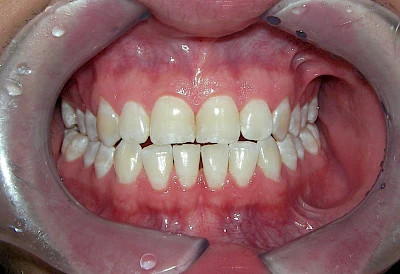

- Durch übermäßige Fluorideinlagerung in der Zahnreifung (mehrere Zähne, weißlich-fleckig)

Daneben gibt es noch seltene genetisch bedingte Schmelz- bzw. Dentinbildungsstörungen (Amelogenesis imperfecta, Dentinogenesis imperfecta), die neben Verfärbungen vor allem auch durch Veränderungen der Oberflächenstrukturen auffallen. In diesen Fällen ist eine engmaschige Betreuung durch den Zahnarzt wichtig.